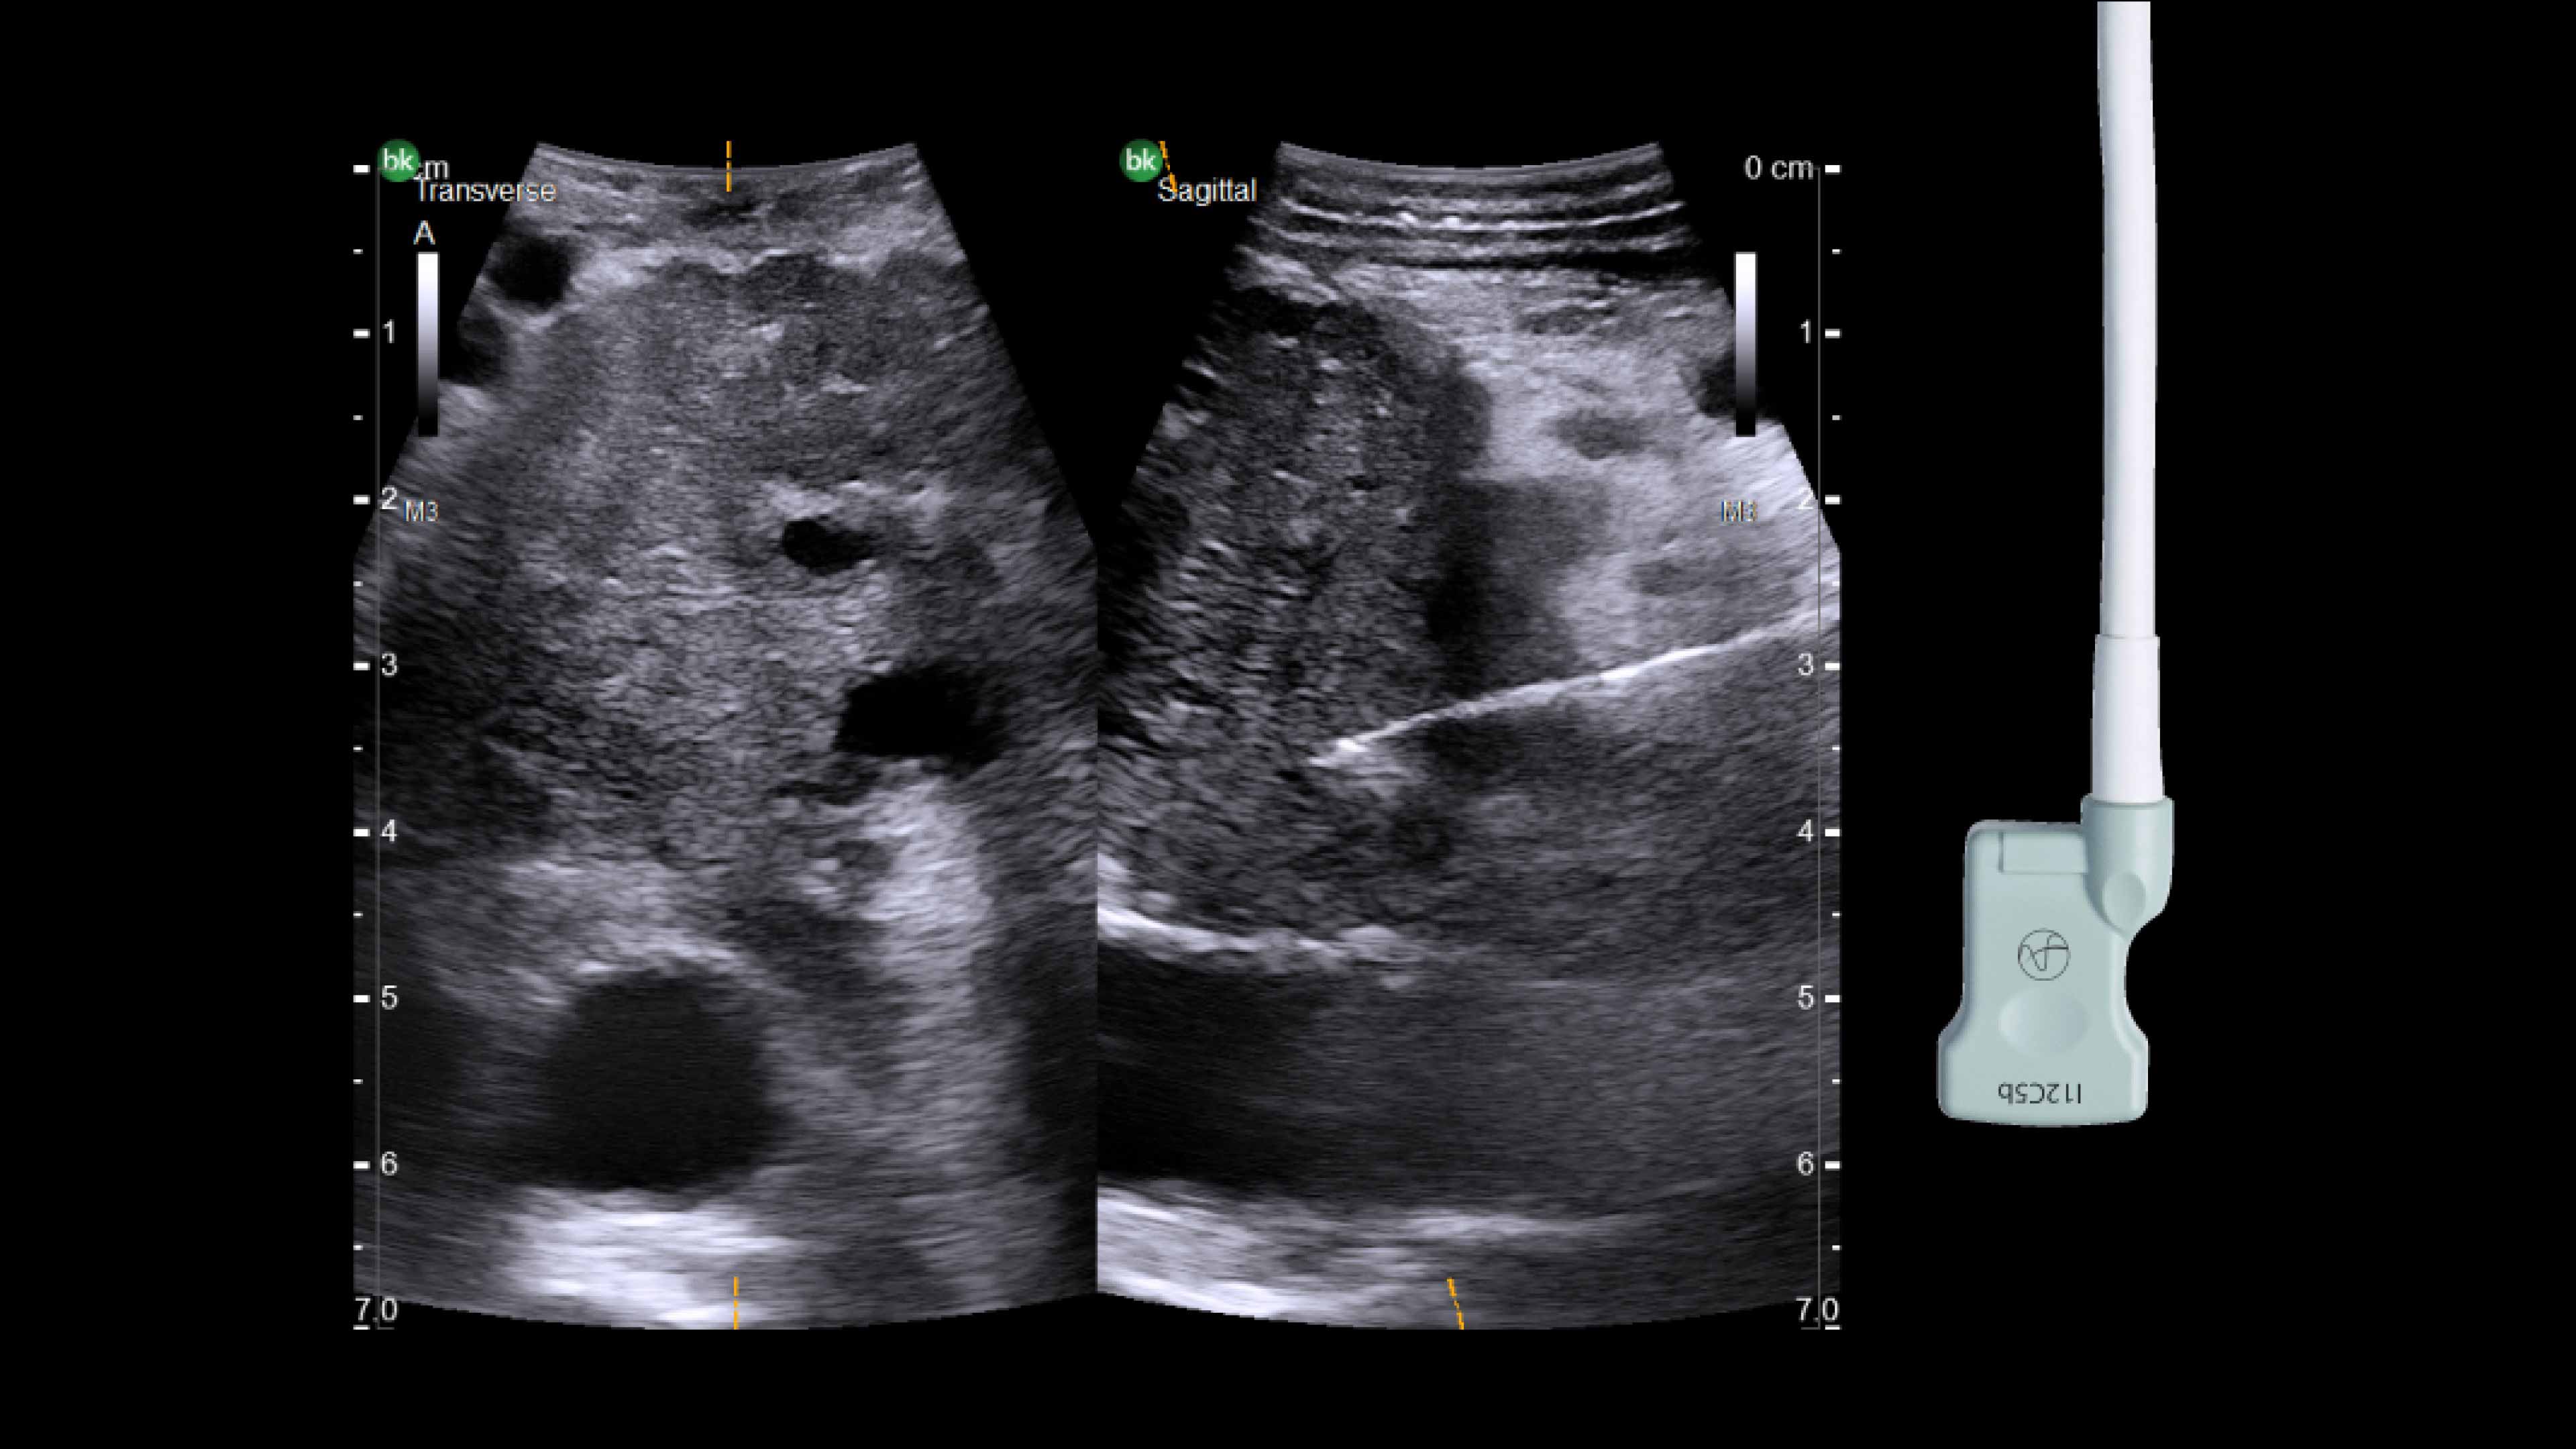

Active imaging with intraoperative ultrasound supports critical decision-making in open or minimally invasive tumor resections.

• Enable visualization of disease staging at the time of surgery with excellent image quality.

• Visualize complex anatomical variations and identify tumor location.

• Define adequate margins of resection.

• Guide and view needle placements.

• Assess surgical planning and check for vessel patency at the end of the procedure.